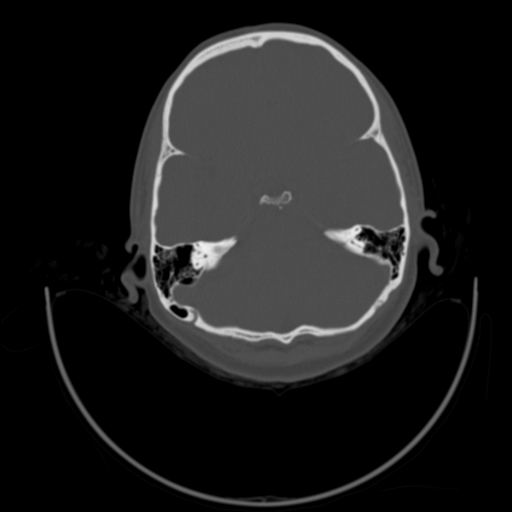

以下是引用随光逐影在2009-3-14 7:58:00的发言:[br]双耳——颞骨ct轴位平扫未见明确异常。

以下是引用杀毒软件在2009-3-14 8:55:00的发言:[br]未见明显异常